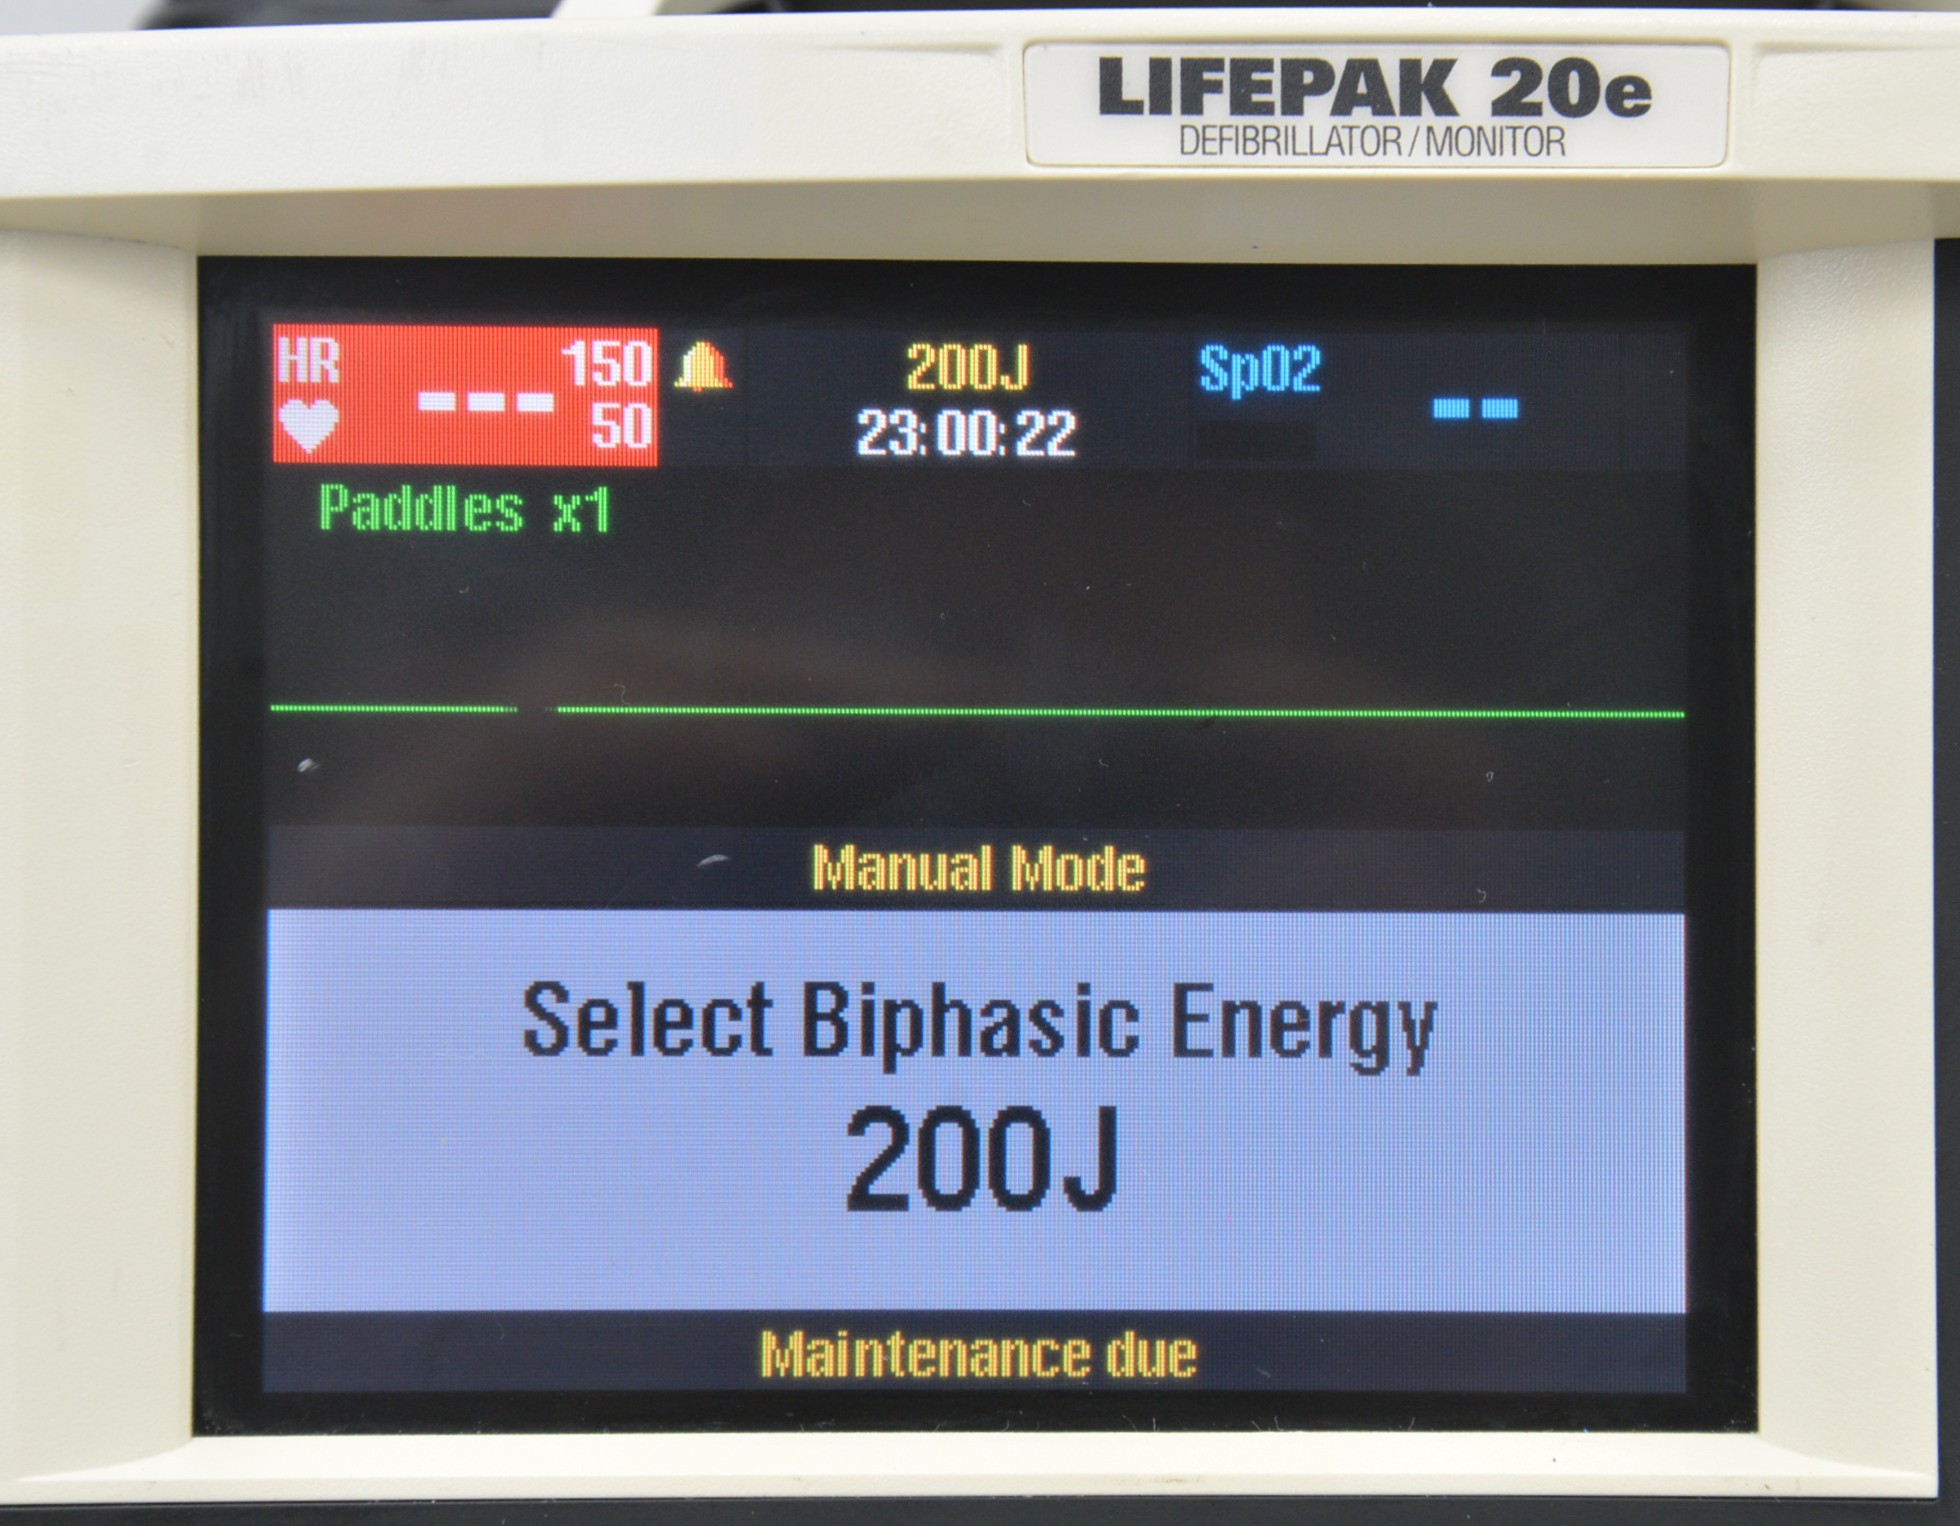

This Medtronic Lifepak 20e Defibrillator Monitor 2010 W/ Paddles is in good working condition. The unit powers on properly and responds to selections. All connection points are clean and in good condition. There are some scuff marks from previous use (see photos). This unit comes with a 30 day satisfaction guarantee. Includes everything in the pictures and nothing else.